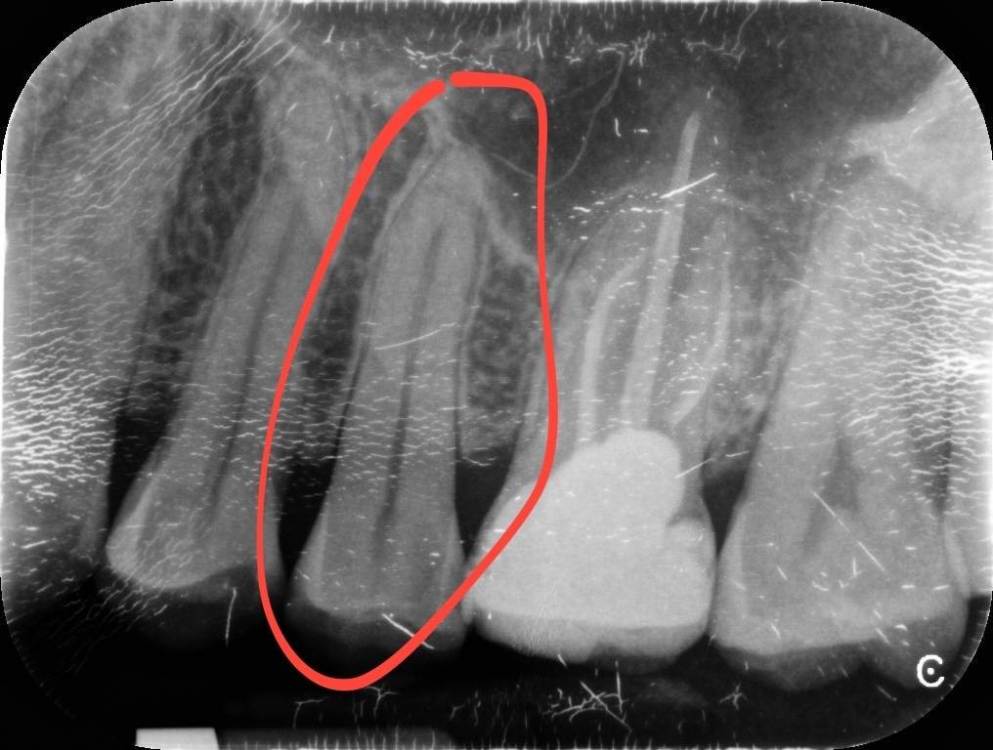

randomsctions Опубликовано 22 апреля, 2023 Автор Поделиться Опубликовано 22 апреля, 2023 Стучали все три врача, но разницы никакой я не заметил. вчера сделали тест: ввели небольшое количество анестетика под каждый зуб с перерывом в 10 мин, чтобы посмотреть, когда утихнет боль. идентифицировали вот этот зуб таким оьразом (оьвёл красным на картинке). Удалили нерв и запломбировали канал. Боль изменилась, но не прошла. Накатывает волнами теперь от почти 0 до 7 по 10-бальной шкале, с периодом около 30 мин +-. Но хотя бы могу спать теперь. Всё ещё буду рад советам, т.к. до сих пор непонятно, в чем проблема. Ссылка на комментарий

randomsctions Опубликовано 24 апреля, 2023 Автор Поделиться Опубликовано 24 апреля, 2023 Добрый день! Наконец-то уговорил врачей сделать КТ. При постукивании, если внимательно прислушиваться, выделяется нижний зуб (обвел красным), ну и верхний депульпированный. Дантист быстро показала КТ эндодонтисту, оба врача ничего страшного там не увидели. Боль продолжается, в состоянии покоя снижается до 1-2, после еды или воды возрастает до 7-8, потом плавно возвращается к 1-2. 741021604_AndreiTiupovCBTCscan.dcm Ссылка на комментарий

Carioznik Опубликовано 25 апреля, 2023 Поделиться Опубликовано 25 апреля, 2023 (изменено) 22.04.2023 в 18:08, randomsctions сказал: Удалили нерв и запломбировали канал сейчас там временная пломба? Судя по КТ - каналы не до конца сделаны. (от этого могут сохраняться боли) На зубе 26 (верхний с большой пломбой) - приличный очаг воспаления из-за пропущенного, когда-то при лечении зуба, канала. Каналы в нём перелечить можно , но есть вопрос с восстановлением и дальнейшим прогнозом (от зуба скорее всего ничего не останется и восстановить его уже не получится нормально , соответственно есть вероятность удаления зуба) 18 часов назад, randomsctions сказал: При постукивании, если внимательно прислушиваться, выделяется нижний зуб Возможно есть рецидив кариеса под пломбой , но это только предположение, нужен очный осмотр. (вряд-ли он причина ваших проблем, но я бы взял его на заметку) еще бы верхний предпоследний более детально посмотреть (очно и доп.прицельный снимок) пока вывод такой: долечить зуб , где удалили нерв. Далее переходить к верхнему зубу с большой пломбой. PS сделайте хоть фотографию во рту, если получится. может что-то еще прояснится Изменено 25 апреля, 2023 пользователем Carioznik 1 Ссылка на комментарий